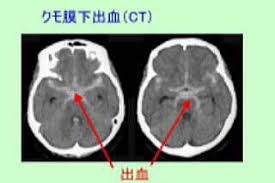

くも膜下出血のctç

くも膜下出血のctç"»åƒã¨è§£å‰– つねぴーblog 内ç§'å°‚æ"»åŒ» from cdn-ak.f.st-hatena.com